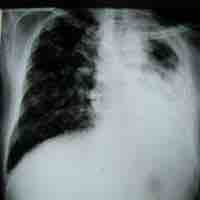

Antimycobacterial antibiotics target microbes classified as mycobacterium.